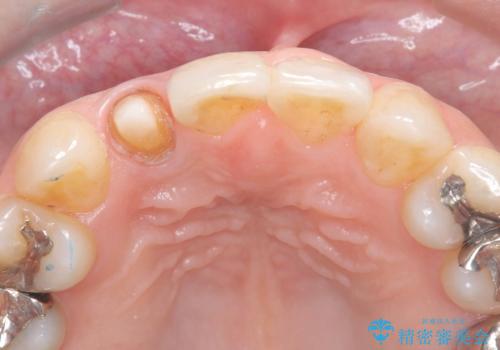

- 「前歯の見た目が気になる」を主訴に来院された患者様です。

失活歯による歯の変色とCR(コンポジットレジン)の劣化による審美不良でした。

オールセラミッククラウンで治療し見た目の改善を行いました。

まず劣化したCRと虫歯を除去した後、仮歯に置き換えました。歯のマージンラインを綺麗に削り光沢が出るまで研磨した後にオールセラミッククラウンの型取りを行っています。